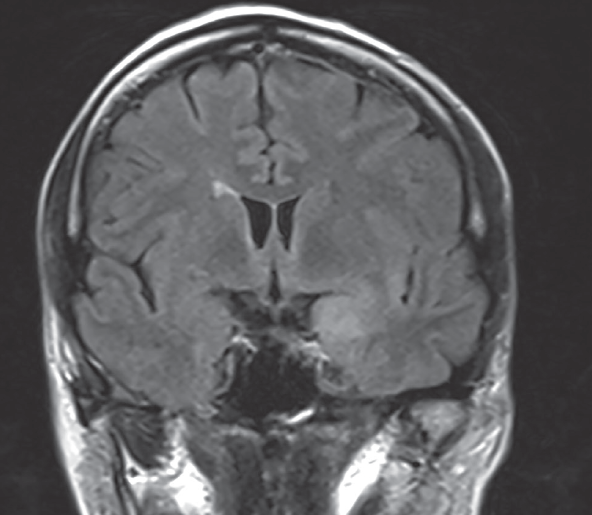

Farah Khan, MD; Richard H. Schwartz, MD, DO; Rebecca Levorson, MD

A 2-year-old girl was diagnosed with S dysgalactiae brain abscess, meningitis, and cerebritis, possibly from a recent middle ear infection.